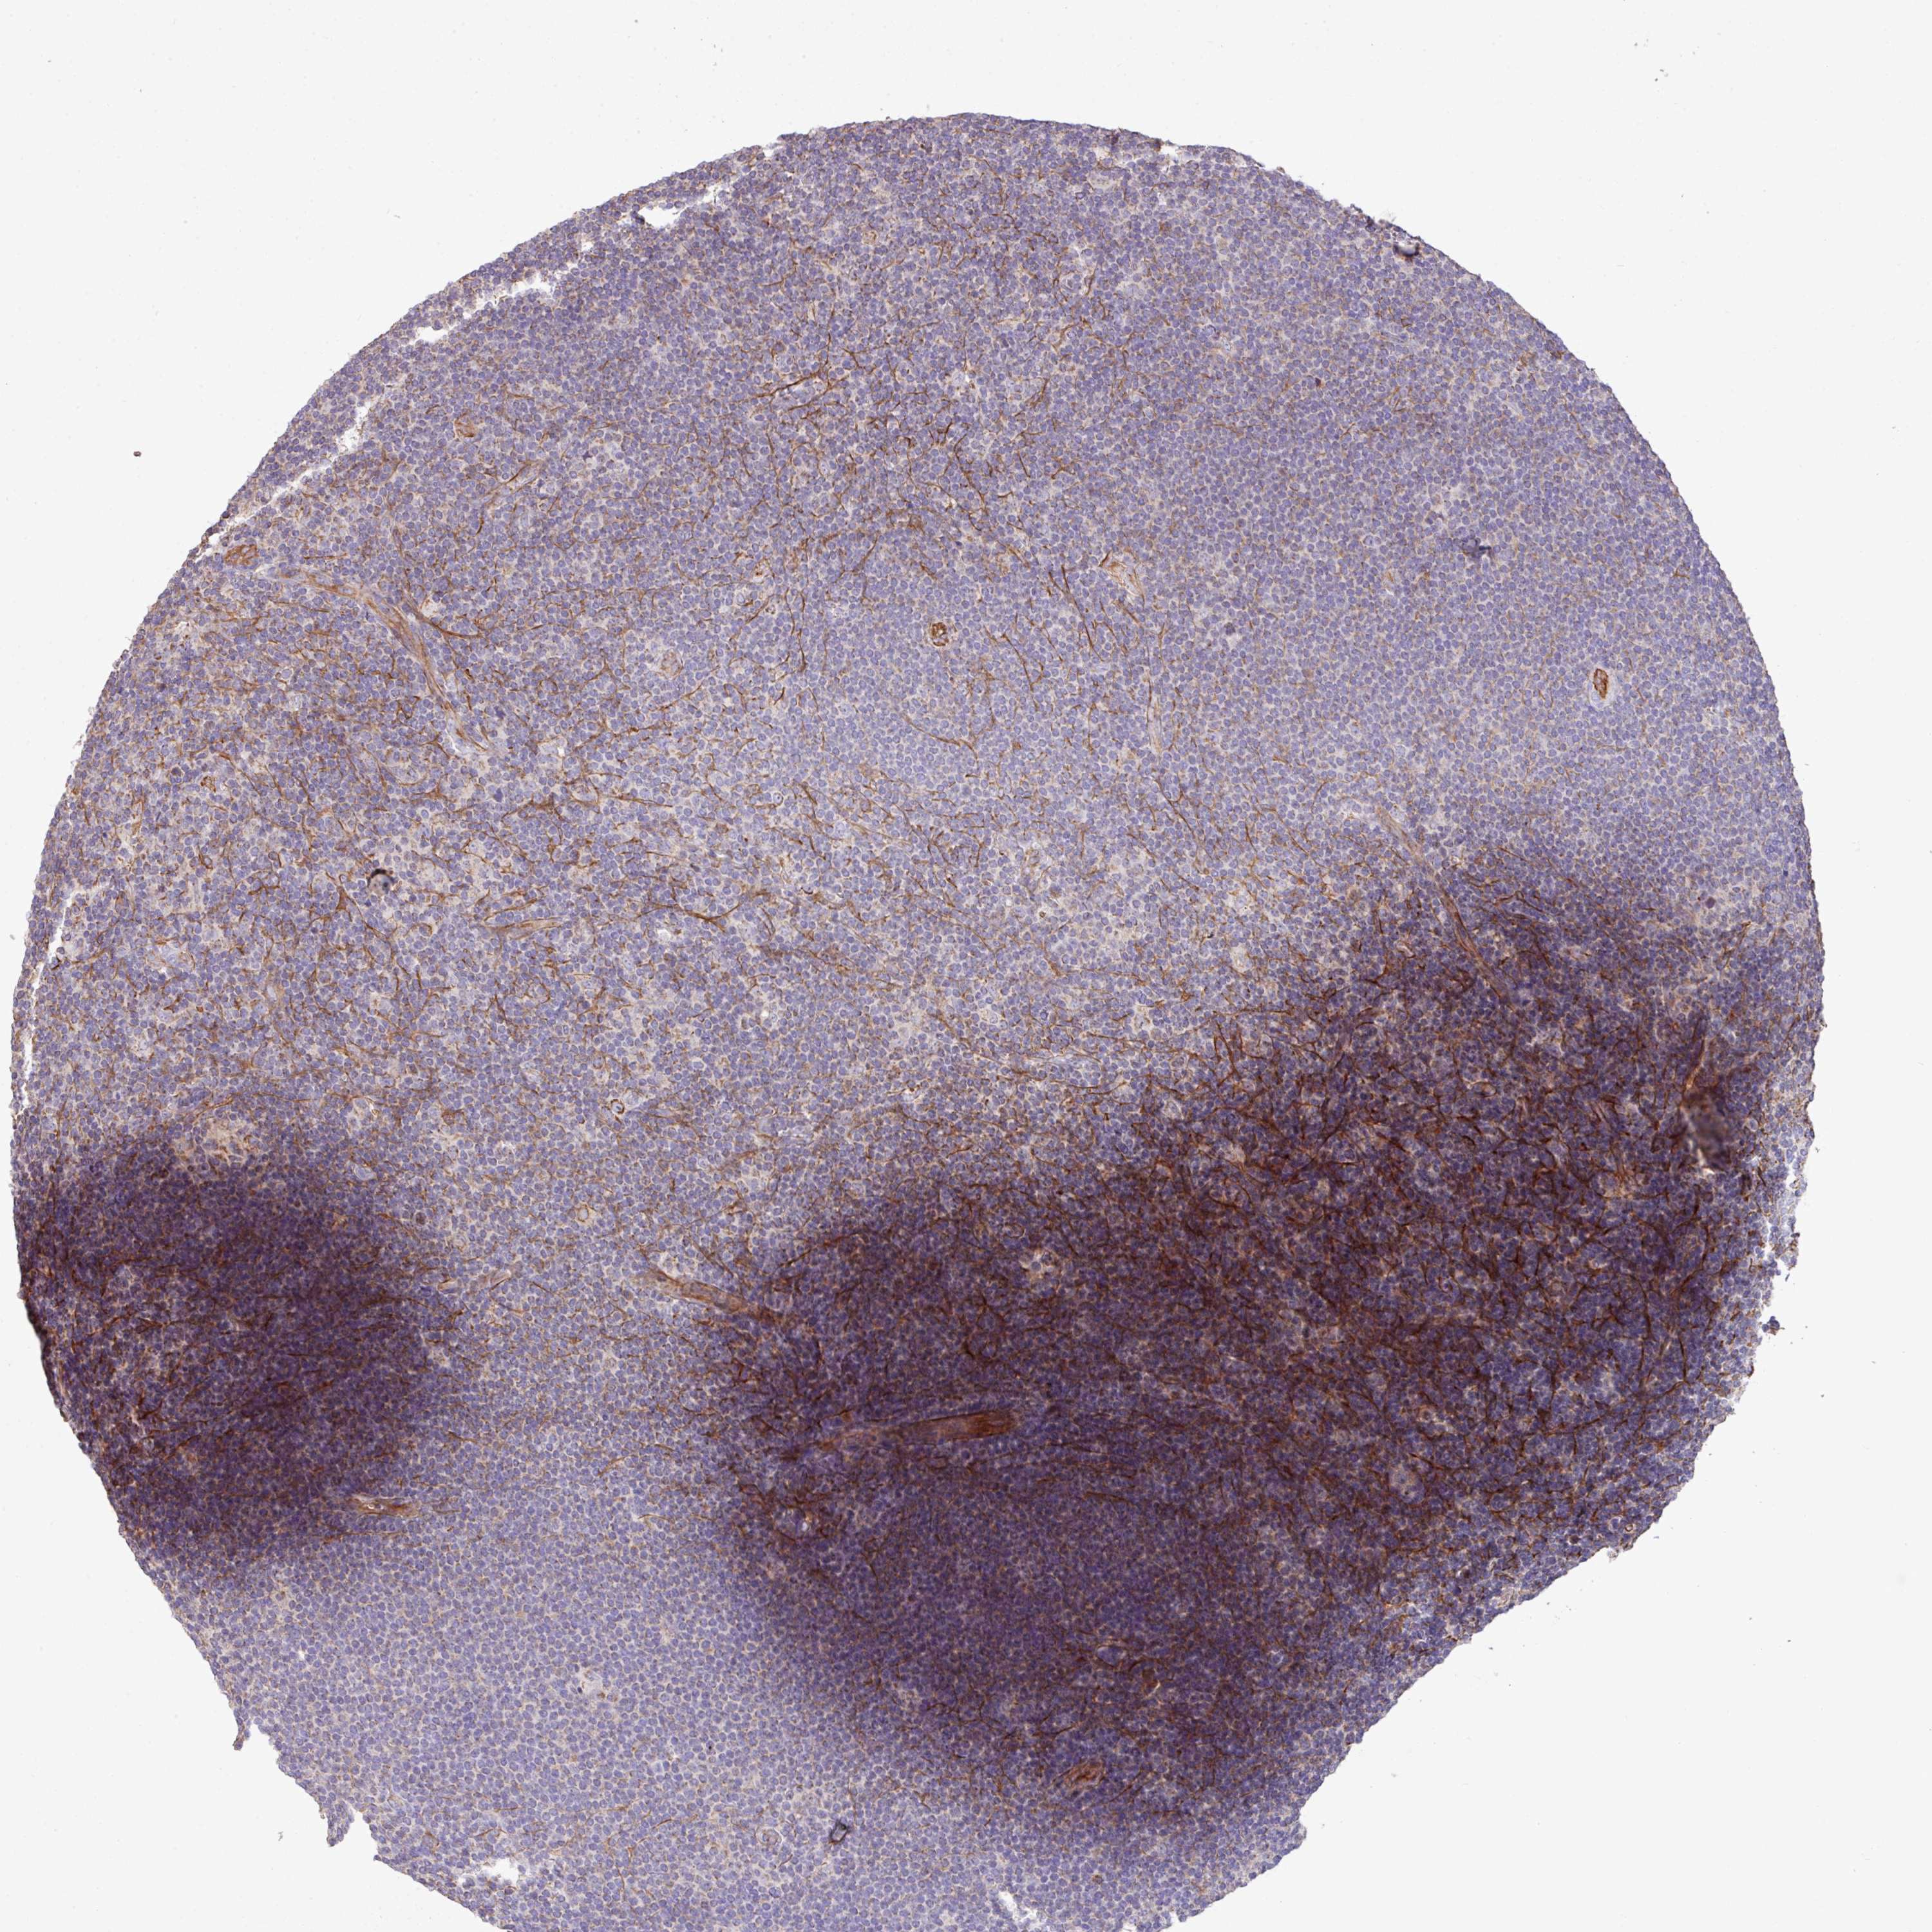

LYMPHOMA - Protein expressioni

A mouse-over function shows sample information and annotation data. Click on an image to view it in a full screen mode. Samples can be filtered based on level of antibody staining by selecting one or several of the following categories: high, medium, low and not detected. The assay and annotation is described here.

Antibody staining in the annotated cell types in the current human tissue is reported as not detected, low, medium, or high, based on conventional immunohistochemistry profiling in selected tissues. This score is based on the combination of the staining intensity and fraction of stained cells.

Each image is clickable and will lead to virtual microscopy that enables deeper exploration of all samples and also displays staining intensity scores, fraction scores and subcellular localization as well as patient and tissue information for each sample.

Antibody HPA054062

Staining

High

Medium

Low

Not detected

Intensity

Strong

Moderate

Weak

Negative

Quantity

>75%

75%-25%

<25%

None

Location

Nuclear

Cytoplasmic/membranous

Cytoplasmic/membranous,nuclear

Hodgkin's disease, NOS

Malignant lymphoma, non-Hodgkin's type, High grade

Malignant lymphoma, non-Hodgkin's type, Low grade